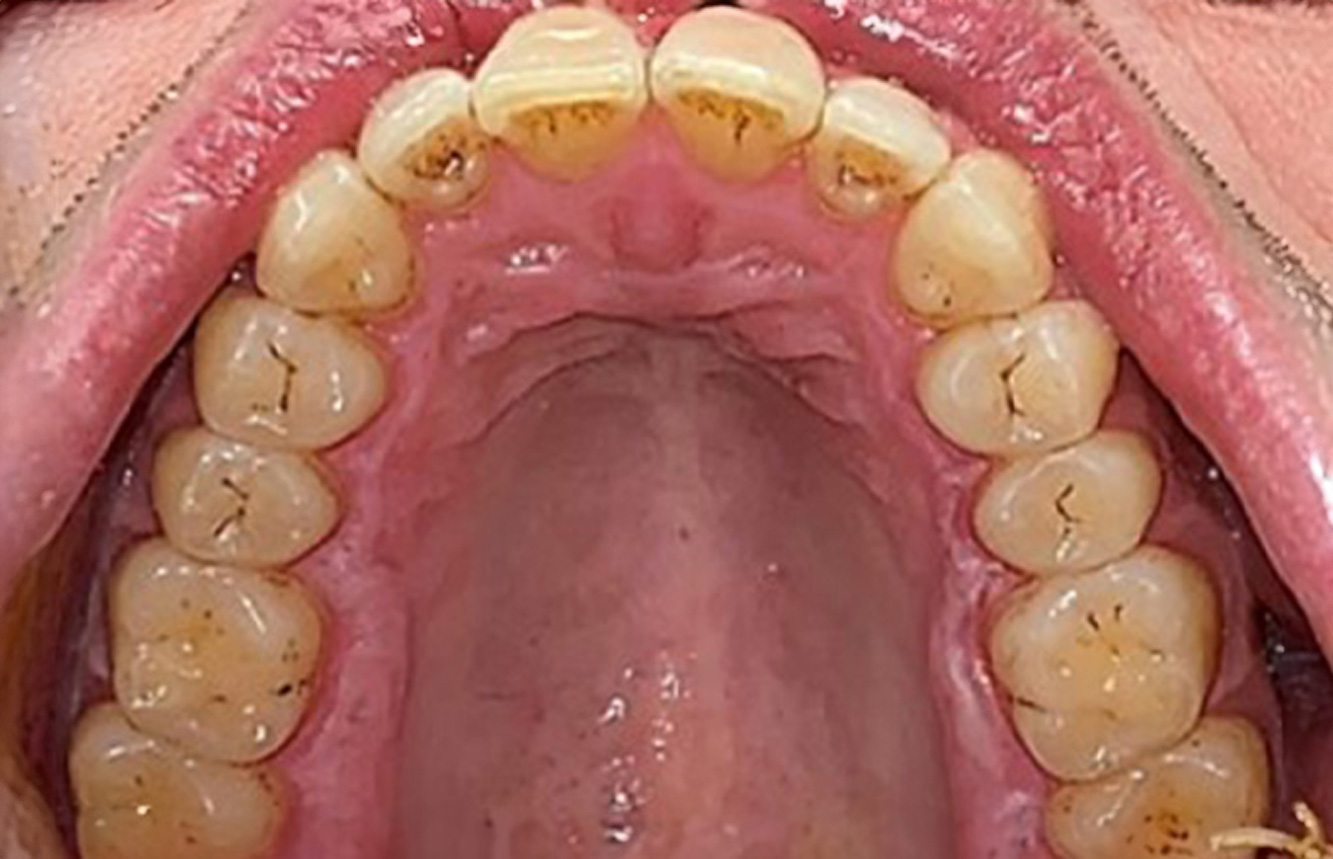

In the medical history, the 55-year-old patient states that he has no systemic disease and is not taking any medication. The patient’s lifestyle is similarly unremarkable. The patient has a few tooth restorations and two implants (2nd and 4th quadrants). On the basis of current findings, gingivitis is identified in an otherwise stable periodontal condition on the reduced periodontium (stage III, grade A). more

A 71-year old patient presents with having previously undergone a kidney transplant and with a history of hypertonia (high blood pressure). Due to his medical history, long-term medication with cyclosporine is required to suppress the immune system, as well as amlodipine to lower blood pressure. The patient also reports sensitive and bleeding gums. From an oral health perspective, the patient has undergone dental restoration and has eight missing teeth, pronounced gingival growth, and grade B, stage II periodontitis with active pockets and initial root caries on tooth 22. The caries risk assessment determines a moderate risk of caries (API 60). The following treatment recommendations can be determined for the prophylaxis session. more

The healthy patient with early periodontal disease